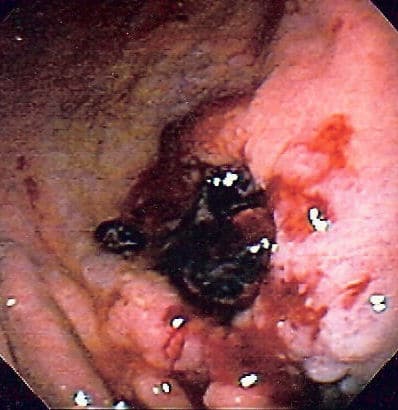

Oesophageal varices refer to dilations of the porto-systemic anastomoses in the oesophagus. They most commonly occur due to portal hypertension secondary to liver cirrhosis and are prone to rupture.

The most common underlying cause for oesophageal varices is alcoholic-related liver disease (ArLD), however can occur with any patient with chronic liver disease. Any melena occurring in a patient with a known chronic liver disease should be urgently investigated for potential variceal bleeding.